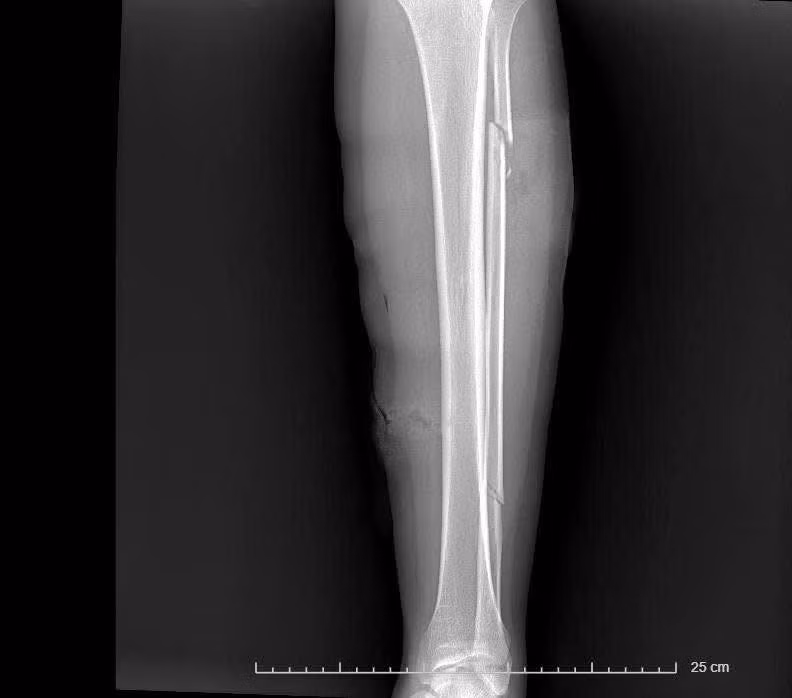

Chụp X-quang: Hình ảnh mất liên tục 1/3 trên và 1/3 dưới xương mác trái, chưa thấy tổn thương khớp gối – cổ chân.

Hình ảnh xương gãy trên phim chụp - Ảnh BVCC